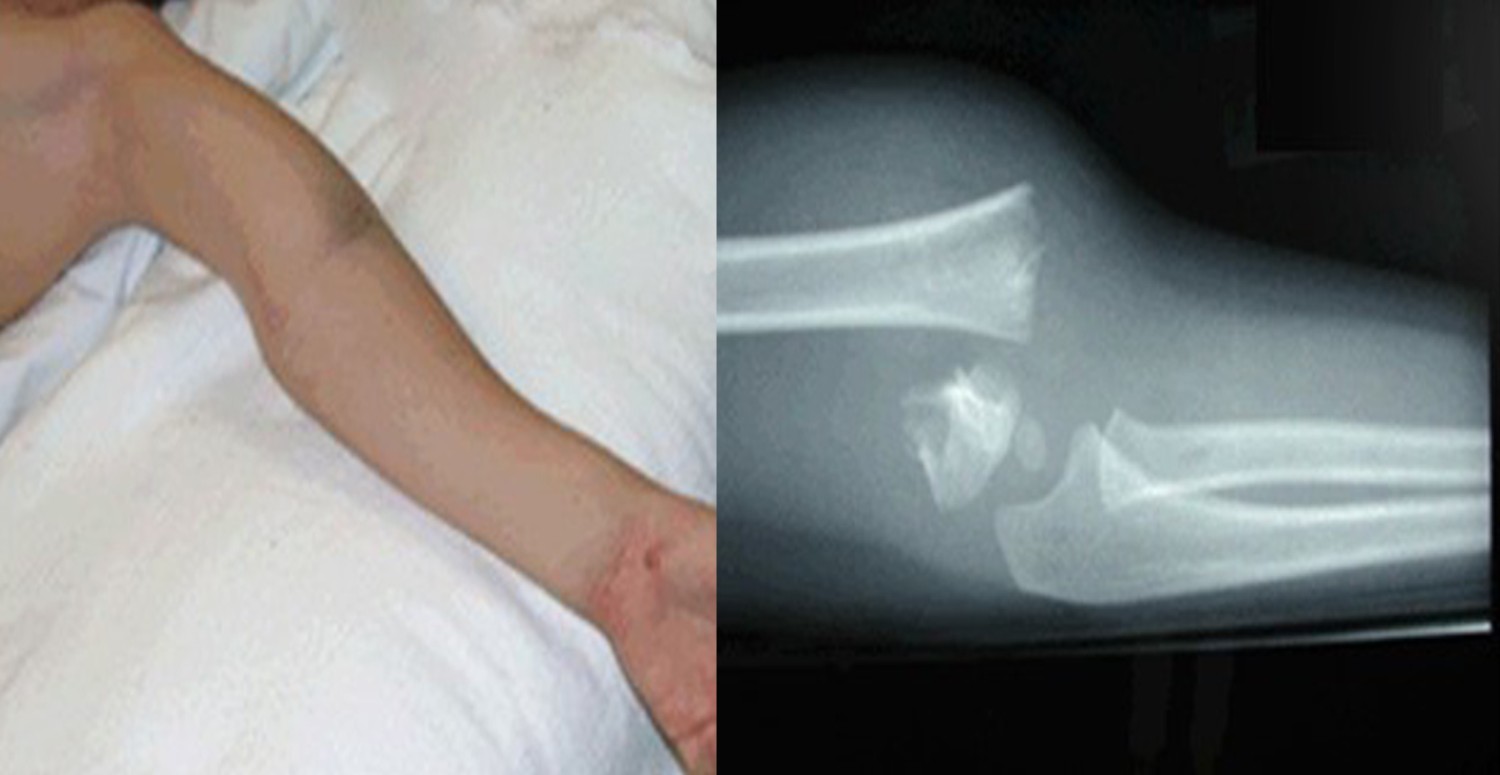

Dirsek çıkığı, çocuklarda sıkça görülen ve acil servisleri dolduran bir durumdur. Dirsek çıkığı, çocukların kolunu kullanamamasına, şiddetli ağrıya ve hatta ömür boyu sakat kalmasına neden olabilir. Peki dirsek çıkığı nedir ve nasıl oluşur? Tedavisi ve korunma yöntemleriyle ilgili tüm bilgiler haber içeriğimizde...

Dirsek çıkığı, tıbben radius kemiğinin başının kısmi çıkığı olarak tanımlanır. Dirsek eklemi, üst kol kemiği (humerus), ön kolun dış tarafındaki kemiği (radius) ve ön kolun iç tarafındaki kemiği (ulna) bir araya getiren bir eklemdir. Dirsek eklemi, kolun bükülmesi, düzleştirilmesi ve döndürülmesi gibi hareketleri sağlar.

Dirsek çıkığı, genellikle 6-7 yaşından daha küçük çocukların el bileklerinden aniden çekilmeleri sonucunda oluşur. Bu ani çekme, henüz tam gelişmemiş ve esnekliğini koruyan dirsek ekleminde ön kolun rotasyonlarının yapıldığı eklemde çıkık oluşturur.

Dirsek çıkığı, çocukların kolunu kıpırdatmak istememesi, şiddetli ağlama ve dirseğini bükük tutması gibi belirtilerle kendini gösterir. Çocuklar, dirseklerini bükük tutarak eklemin yerine oturmasını sağlamaya çalışırlar. Dirsek çıkığı, genellikle acil servislere başvurulan bir durumdur.

Dirsek çıkığı, tedavisinde çıkık olan eklemin özel bir teknikle yerine oturtulma manevrası yapılır. Bu manevra, hekim tarafından uygulanır ve genellikle çocukta bir anda rahatlama yaşanır. Birkaç dakika sonra çocuk kolunu kullanmaya başlar. Bazen röntgene yollanan olgularda çekim sırasındaki pozisyonlama nedeniyle eklemin kendiliğinden yerine oturmasıyla da karşılaşılabilir. Dirsek çıkığı, bir defa yaşanmışsa tekrar etme riski vardır.